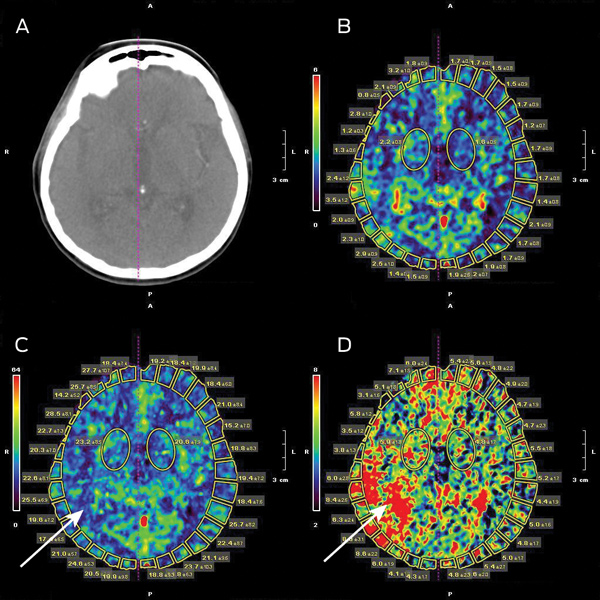

The local hospital acute stroke treatment protocol was followed, commencing with attendance by a code stroke team. Conventional non-contrast computed tomography (CT) of the brain performed 2 hours after symptom onset showed subtle and early obscuration of the right posterior insular cortex (Box 1). Findings on perfusion CT (Aquilion One, Toshiba Medical Systems, Otawara, Japan) were consistent with a large area of ischaemic penumbra in a right posterior middle cerebral artery (MCA) distribution (Box 2), corresponding to a right MCA (M2 segment) thrombotic occlusion on CT angiography.